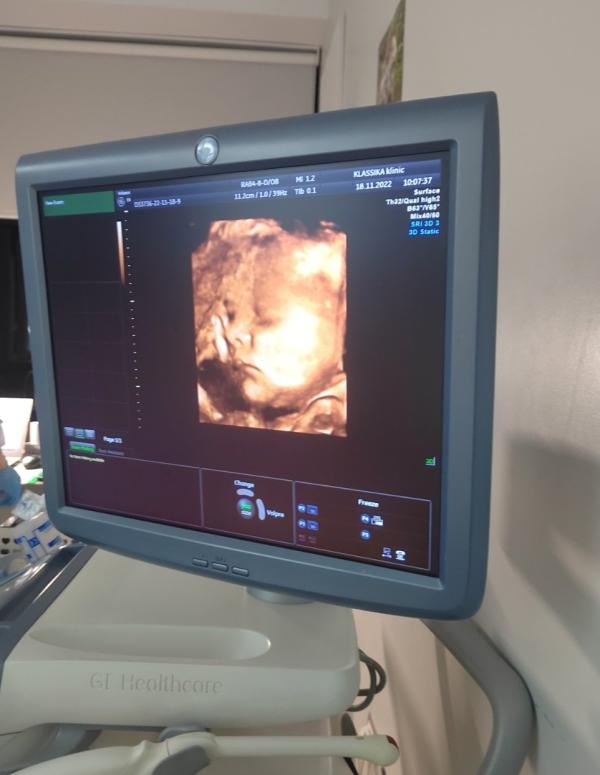

Вот она наша серьёзная девочка❤️ Наша маленькая доченька🙏 Господи какое это счастье! Эти пухлые щёчки, носик, второй подбородочек, а губки и серьезное личико во сне как у папы😍 Так и хочется уже потискать😋🤗

Это был наш 3 скрининг. Проходили мы его в клинике "Классика". Узист Аухтун Ю. М. Это просто узист от Бога!!! Она нереально классная!!! Сразу видно, что человек любит свою работу: всё объяснила, показала, ну такая она невероятная😍

Пусечка наша весит 2200 +- 320 гр, 45 см. Узист сказала, что к родам наша крошка будет кг 4😁 Хорошо, говорит, мамочка заиньку кормит, такие щечки уже😁 Лежит головкой вниз моя умничка🙏 Весь скрининг проспала с ручкой под щёчкой ❤️